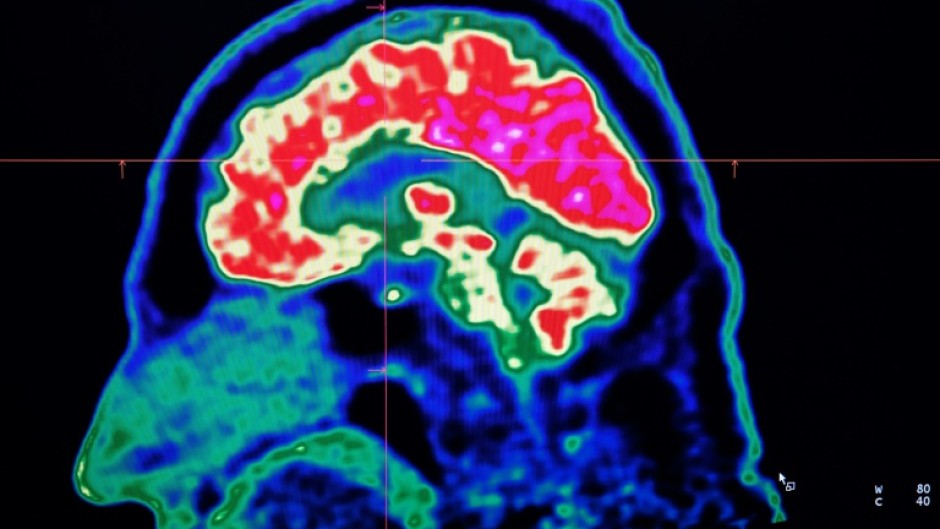

WASHINGTON - Conditions affecting the nervous system -- such as strokes, migraines and dementia -- have surged past heart disease to become the leading cause of ill health worldwide, a major new analysis said on Friday.

More than 3.4 billion people -- 43 percent of the global population -- experienced a neurological condition in 2021, far more than had previously been thought, the analysis found.

The researchers looked at how 37 different neurological conditions affected ill health, disability and premature death across 204 countries and territories from 1990 to 2021.